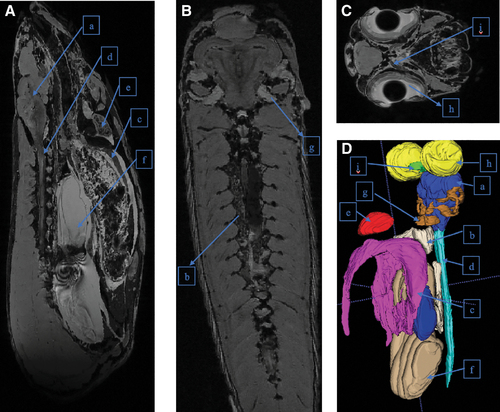

MRIs of 9-month-old WT zebrafish with (1A) sagittal, (1B) axial, (1C) coronal sections, and (1D) 3D reconstruction. Organs analyzed include (a) brain, (b) kidneys, (c) liver, (d) spinal cord, (e) heart, (f) swim bladder, (g) ears/otolith organ, (h) eyes, and (i) optic nerve. 3D, three-dimensional; MRI, magnetic resonance imaging; WT, wild type. |